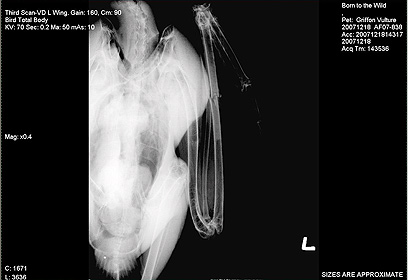

צילום הרנטגן של "אורנה" (באדיבות: בית החולים לחיות בר)

"... גילינו שכדורית ירי היתה תקועה באזור בסיס הזנב", הסביר שמוליק לנדאו, איש צוות בית חולים בשלוחת אפק. "היא היתה חלשה ובמתח גדול. בימים הראשונים בטיפול כמעט שלא אכלה".

הצוות הרפואי קיבע את הכנף ולאחר אישפוז קצר הועברה אורנה לחי-בר כרמל, כדי לשקם את יכולות התעופה שלה בכלוב תעופה מיוחד. "למרות שיש לה בגוף כדורית ירי, כל עוד היא לא מגיעה למחזור הדם לא נשקפת לה סכנה. למרבה השמחה, היא השתקמה תוך מספר חודשים באופן מלא והושבה לכלוב האיקלום בשמורה", סיכם לנדאו.